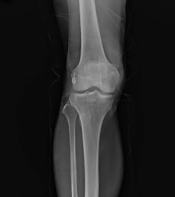

6. 척추 건강 지원

글루코사민은 척추 관절염과 관련된 통증과 뻣뻣함을 감소시키는 데 효과적입니다. 척추의 유연성을 향상시키고, 척추 주변의 연골 건강을 지원함으로써 전반적인 척추 건강을 개선할 수 있습니다.